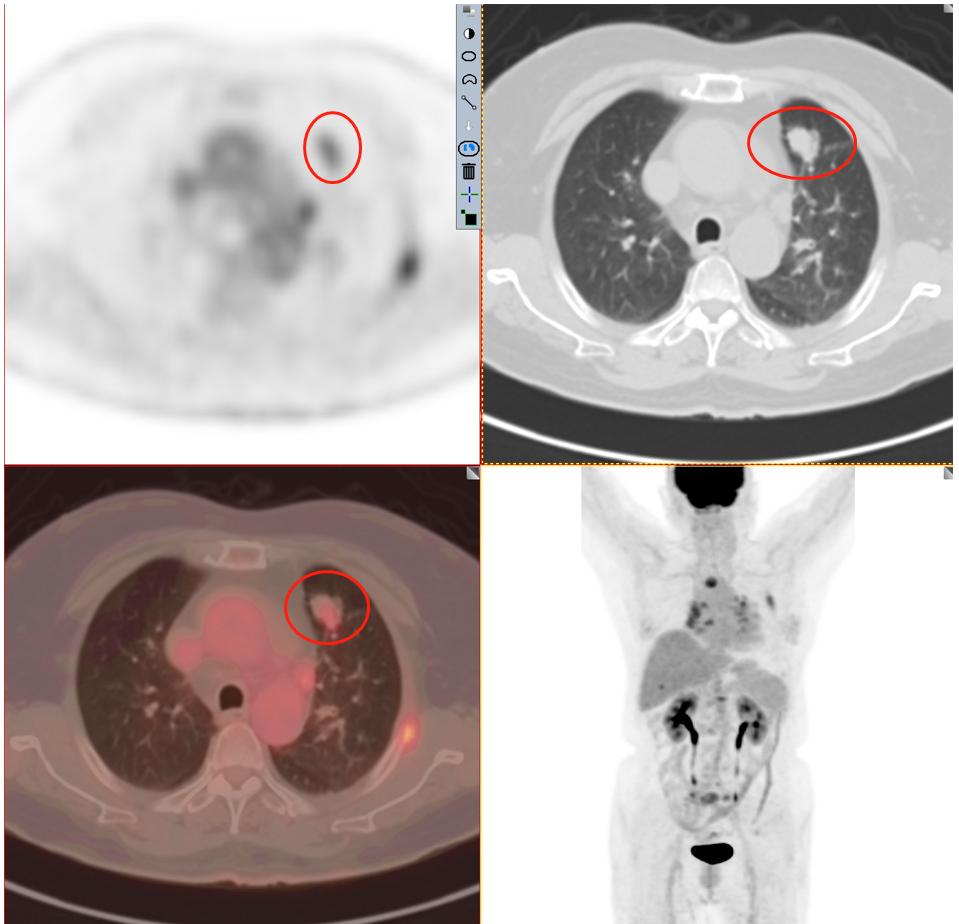

患者1:图3

毫无疑问PET/CT检查18-F-FDG葡萄糖代谢增高,再一次增强了肺癌的诊断信心,影像学可以肯定的诊断为周围型肺癌。其余所示结节未见FDG代谢增高,考虑为慢性炎性结节及钙化灶。